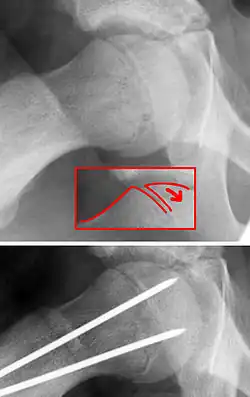

X-ray showing a slipped capital femoral epiphysis, before and after surgical fixation.

The diagnosis requires x-rays of the pelvis, with anteriorposterior (AP) and frog-leg lateral views.[11] The appearance of the head of the femur in relation to the shaft likens that of a "melting ice cream cone", visible with Klein's line. The severity of the disease can be measured using the Southwick angle.

The disease can be treated with external in-situ pinning or open reduction and pinning. Consultation with an orthopaedic surgeon is necessary to repair this problem. Pinning the unaffected side prophylactically is not recommended for most patients, but may be appropriate if a second SCFE is very likely.[11]

Once SCFE is suspected, the patient should be non-weight bearing and remain on strict bed rest. In severe cases, after enough rest the patient may require physical therapy to regain strength and movement back to the leg. A SCFE is an orthopaedic emergency, as further slippage may result in occlusion of the blood supply and avascular necrosis (risk of 25 percent). Almost all cases require surgery, which usually involves the placement of one or two pins into the femoral head to prevent further slippage.[12] The recommended screw placement is in the center of the epiphysis and perpendicular to the physis.[13] Chances of a slippage occurring in the other hip are 20 percent within 18 months of diagnosis of the first slippage and consequently the opposite unaffected femur may also require pinning.

The risk of reducing this fracture includes the disruption of the blood supply to the bone. It has been shown in the past that attempts to correct the slippage by moving the head back into its correct position can cause the bone to die. Therefore the head of the femur is usually pinned 'as is'. A small incision is made in the outer side of the upper thigh and metal pins are placed through the femoral neck and into the head of the femur. A dressing covers the wound.